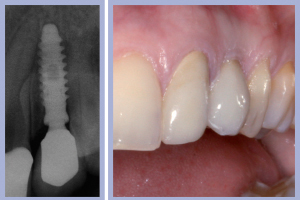

- Figg. 11a, b – Inserimento dell’impianto di destra. Max Stability da 3,75 x 12 mm

- Figg. 12a, b – Impianto di destra inserito

Il posizionamento di due impianti Max Stability da 3,75 mm di diametro e 12 mm di lunghezza ha consentito l’ottenimento di una elevata stabilità primaria, essenziale per portare a termine il carico immediato programmato. Nel caso dell’impianto Max Stability, la forma tronco-conica è associata alla presenza di spire molto prominenti che garantiscono un’elevata stabilizzazione anche in osso di qualità scadente.

La valutazione clinica al momento della consegna dei manufatti e clinico-radiologica a 3 mesi dalla consegna manifestava una completa integrazione tissutale con eccellente recupero estetico e funzionale (Figg. 29-30).

- Figg. 29a, b Manufatti di destra e radiografia di controllo. Si noti l’ottima integrazione tissutale

- Figg. 30a, b – Manufatti di sinistra e radiografia di controllo